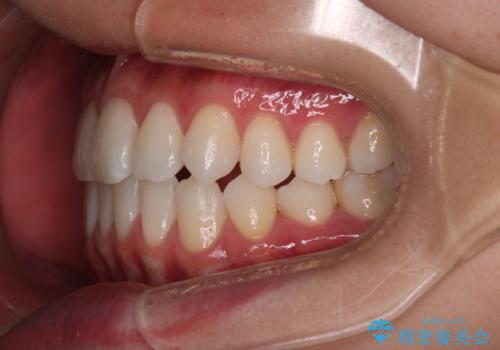

- 右上2番が欠損しており、歯並びをバランスよくしたいということで来院されました。

ワイヤー装置とマウスピースで悩まれていましたが、マウスピースで治療可能と判断致しましたのでマウスピースにて治療しました。

IPR、歯列弓拡大、ゴム掛けを行い歯並びを整える治療計画を立てました。

右上2番が欠損しているため、見た目と噛み合わせの両方のバランスを整えるために経過を追いながら必要な部位にゴム掛けをしました。

最終的に、見た目も噛み合わせも患者様に満足いただけました。